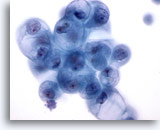

Figure 10

Breast FNA, Fibroadenoma.

A branching sheet of benign ductal cells with overlying myoepithelial cells produce the characteristic ‘sesame seed on a bun’ appearance. 40x

Figure 10

Breast FNA, Fibroadenoma.

A branching sheet of benign ductal cells with overlying myoepithelial cells produce the characteristic ‘sesame seed on a bun’ appearance.

40x